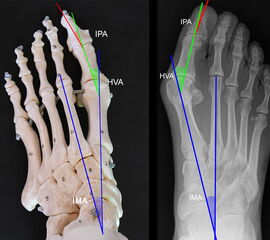

Vermessung der belasteten Aufnahmen des Fußes

Winkelmessungen am Fußskelett beziehen sich sämtlich auf belastete Aufnahmen 6. Die folgenden Aufnahmen zeigen die üblicherweise verwendeten Winkelmaße und ihre Definition. Viele Fehlstellungen des Fußes betreffen den Vor- und Rückfuß. Dies sollte bei der Beurteilung der Bilder und der Therapieplanung stets berücksichtigt werden.

Beurteilung von Fehlstellungen des Vorfußes

Zur Vollansicht und zum Lesen der Bildbeschreibung bitte die Bilder anklicken.

Gelenkflächenwinkel

DMAA (Distal metatarsal artikular angle, Syn. Gelenkflächenwinkel): Winkel zwischen der Achse des Os metatarsale I (rot) und dem Lot auf die distale Gelenkflächenebene (blau) des Os metatarsale I. Die Gelenkflächenebene (grün) wird definiert durch zwei Punkte, welche die mediale und laterale Begrenzung der Gelenkfläche definieren (Norm: <10° 5). Die Projektion des DMAA ist stark abhängig von der Rotation des Os metatarsale I 7. Daher ist bei der operativen Behandlung des Hallux valgus eine Beurteilung häufig erst nach Korrektur der Pronationsstellung des Os metatarsale I möglich. Tendenziell wird der DMAA auf präoperativen Röntgenaufnahmen überschätzt.